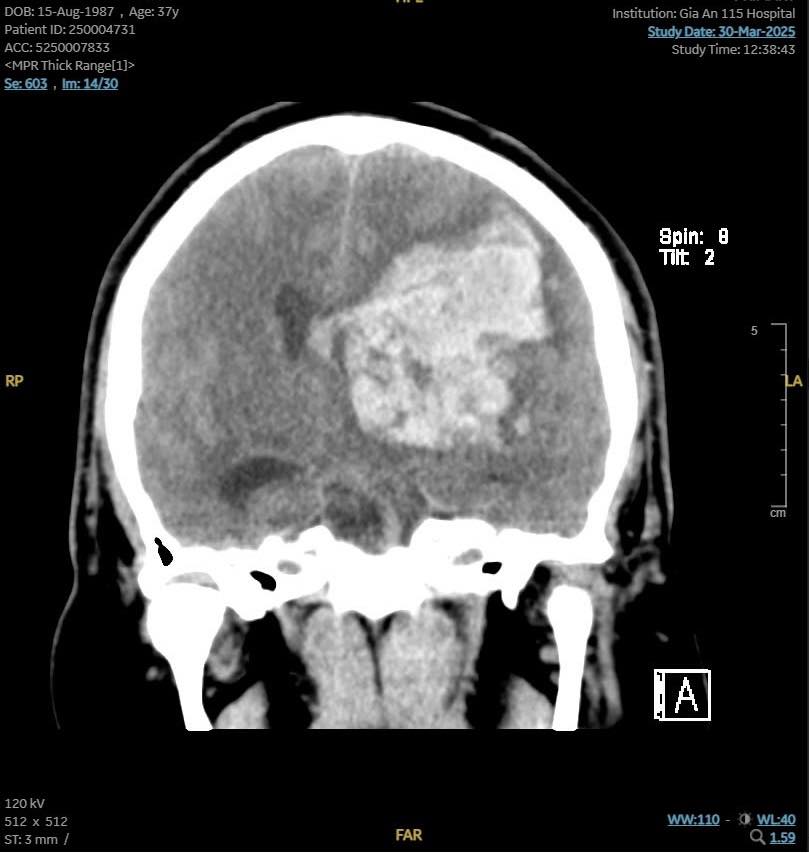

Sau khi cấp cứu hồi sinh tim phổi tích cực, tim bệnh nhân đập trở lại và được chuyển đến bệnh viện. Tại đây, kết quả CT scan cho thấy bệnh nhân bị xuất huyết não lan rộng gần hết bán cầu não trái, tràn vào não thất, gây phù não và đẩy lệch đường giữa, BS Nhật Tuệ cho biết.

Hình ảnh CT scan của bệnh nhân cho thấy tình trạng phù não và đẩy lệch đường giữa (Ảnh: BVCC)